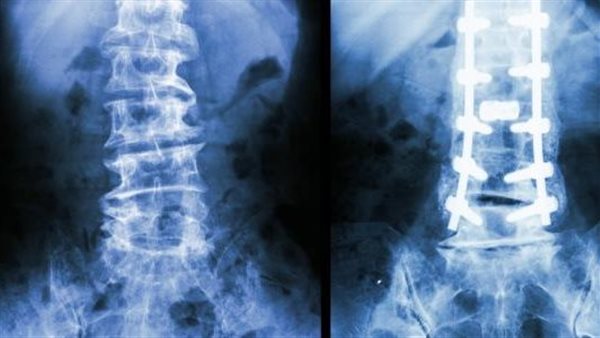

ويعد هشاشة العظام مرض يتميز بضعف العظام وهشاشتها نتيجة فقدان كثافتها، إن الأشخاص الذين يعانون من هشاشة العظام هم الأكثر عرضة لخطر الإصابة بكسر عظام الفخذ، ويمكن للعلاج الدوائي أن يقلل من هذا الخطر بنحو 50%.